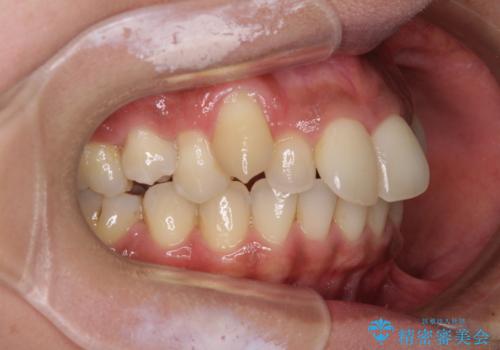

- 八重歯と上下前歯のでこぼこを気にして来院された患者様です。

上下前歯部叢生のスペース獲得のため、上下顎左右小臼歯各1歯(計4本)を抜歯して、ワイヤー装置にて矯正治療を行うこととしました。